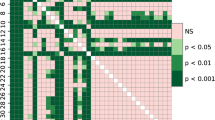

The recall, precision, and F-1 score for detecting maxillary cysts were 74.6%/77.1%, 89.8%/90.0%, and 81.5%/83.1% for the testing 1/testing 2 datasets, respectively. The recall was higher in the anterior regions and for radicular cysts. The sensitivity was higher for identifying radicular cysts than for other lesions.

Using deep learning object detection technology, maxillary cyst-like lesions could be detected in approximately 75–77%.